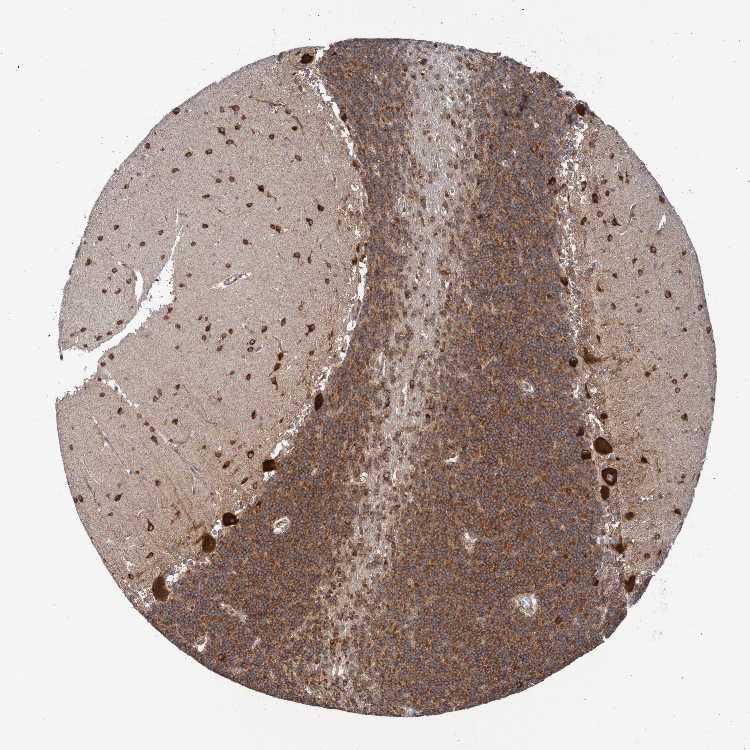

CEREBELLUM - Antibody stainingi

Antibody staining in the annotated cell types in the current human tissue is reported as not detected, low, medium, or high, based on conventional immunohistochemistry profiling in selected tissues. This score is based on the combination of the staining intensity and fraction of stained cells.

Each image is clickable and will lead to virtual microscopy that enables deeper exploration of all samples and also displays staining intensity scores, fraction scores and subcellular localization as well as patient and tissue information for each sample.

Antibody HPA022997Antibody CAB011205

Bergmann glia - cytoplasm/membrane -Medium

Bergmann glia - nucleus -Not detected

GLUC cells - cytoplasm/membrane -High

GLUC cells - nucleus -Not detected

Purkinje cells High-

Purkinje cells - cytoplasm/membrane -High

Purkinje cells - dendrites -Medium

Purkinje cells - nucleus -Not detected

Cells in granular layer High-

Cells in molecular layer High-

Granular cells - cytoplasm/membrane -High

Granular cells - nucleus -Not detected

Molecular layer - neuropil -Not detected

Molecular layer cells - cytoplasm/membrane -High

Molecular layer cells - nucleus -Not detected

Processes in granular layer -Not detected

Processes in molecular layer -High

Processes in white matter -Not detected

Synaptic glomeruli - capsule -Not detected

Synaptic glomeruli - core -High

White matter cells - cytoplasm/membrane -High

White matter cells - nucleus -Not detected